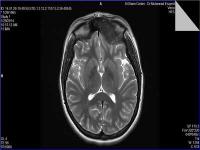

Medical imaging is an important investigative tool will help doctors to reach for the diagnosis of certain diseases, and the the advanced and high-quality imaging technologies are an important factor in maintaining the health of patients and accurate diagnosis of pathological lesions.